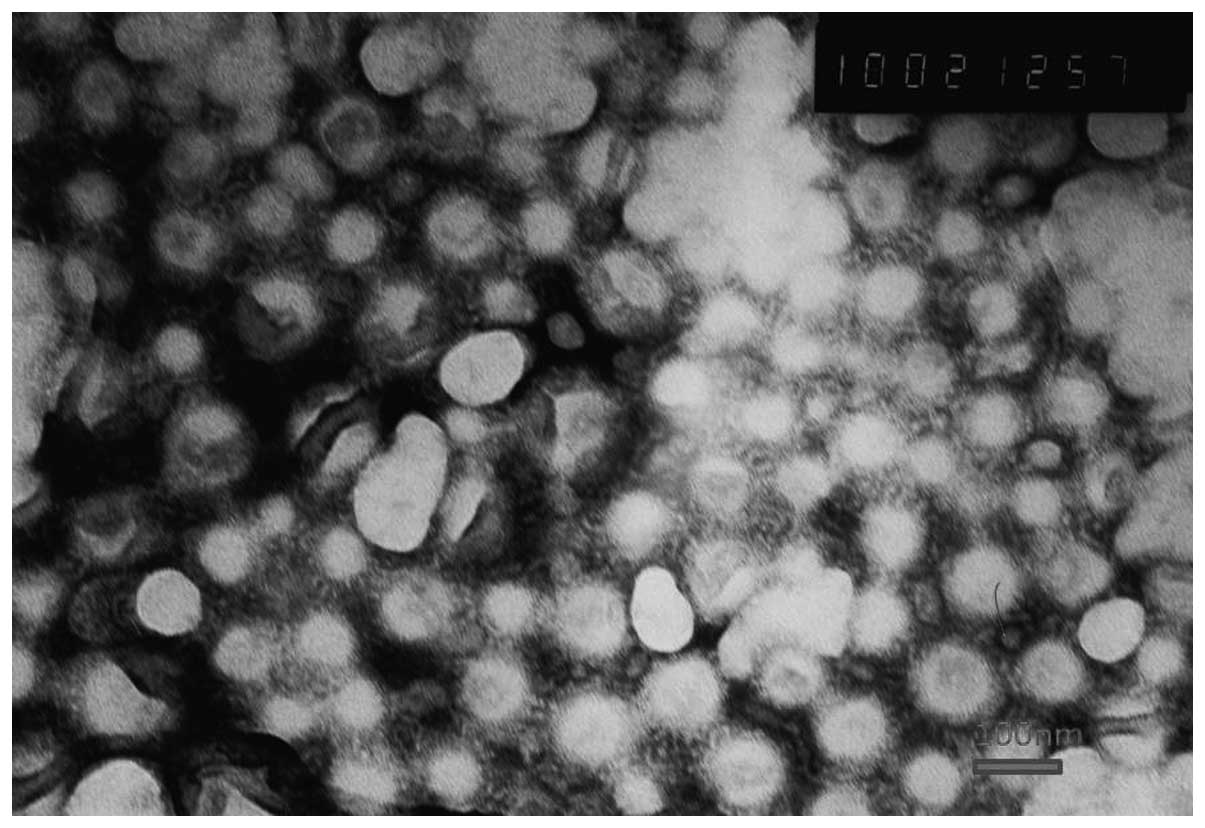

Transferrin-conjugated doxorubicin-loaded lipid-coated nanoparticles for the targeting and therapy of lung cancer

In the present study, a targetable vector was developed for the targeted delivery of anticancer agents, consisting of lipid‑coated poly D,L‑lactic‑co‑glycolic acid nanoparticles (PLGA‑NP) that were modified with transferrin (TF). Doxorubicin (DOX) was used as a model drug for lung cancer therapy. The use of these NPs combined the advantages and avoided the disadvantages exhibited individually by liposomes and polymeric NPs during drug delivery. The lipid coating of the polymeric core was confirmed by transmission electron microscopy. The physicochemical characteristics of transferrin‑conjugated lipid‑coated NPs (TF‑LP), including the particle size, zeta potential, morphology, encapsulation efficiency and in vitro DOX release, were also evaluated. The cellular uptake investigation in the present study found that TF‑LP was more efficiently endocytosed by the A549 cells, than LP and PLGA‑NPs. Furthermore, the anti‑proliferative effect exhibited by DOX‑loaded TF‑LPs on A549 cells and the inhibition of tumor spheroid growth was stronger compared with the effect of DOX‑loaded lipid‑coated PLGA‑NPs and PLGA‑NPs. In the in vivo component of the present study, TF‑LP demonstrated the best inhibitory effect on tumor growth in the A549 tumor‑bearing mice. It was concluded that TF‑LP may be an efficient targeted drug‑delivery system for lung cancer therapy.